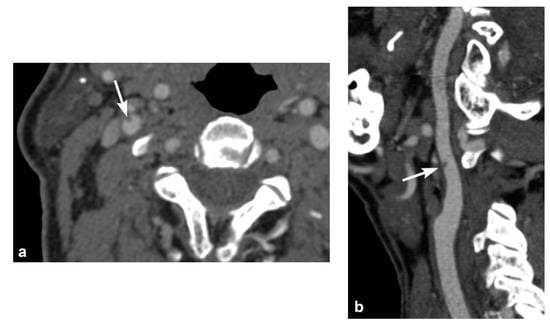

3. Imaging Findings of Arterial Injury